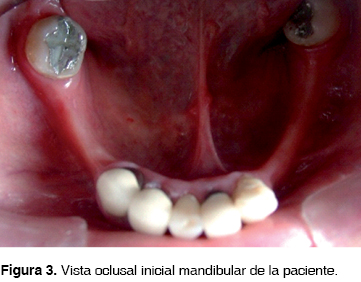

En la exploración dental, la paciente presentaba: ausencia de los dientes: 18, 17, 27, 28, 33, 34, 35, 36, 38, 44, 45, 46 y 48. Tenía aproximadamente 5 años de haberse colocado en los dientes 15, 14, 13, 12, 11, 21, 22, 23, 24, 25, 31, 42 y 43 coronas individuales de metal-porcelana y en el diente 16 una onlay metálica. En caras oclusales de 37 y 47 amalgamas. En 26 muñón con miracle-mix y en mandíbula una prótesis parcial removible flexible, de mayor tiempo, sin tenerse datos exactos (Figuras 1, 2 y 3).

En la mandíbula se observó brecha desdentada clase III de Kennedy con dientes remanentes grado 2 de movilidad, pérdida de soporte óseo e inflamación en zona desdentada (Figura 4).